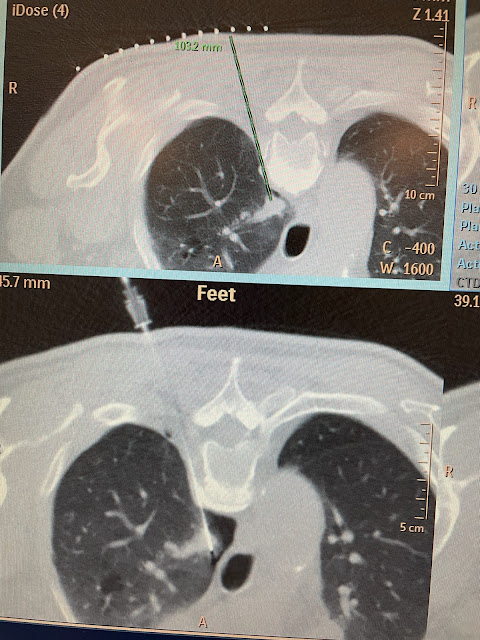

In fact, it was almost a month until just the biopsy in mid March, as there was a complication: a PET CT scan revealed a nodule of cell “activity” in Ariel’s lung. That meant either cancer or a very localised infection, and the latter was rather unlikely. Unfortunately, the lung nodule was close to a notable vein, so the surgeon thought it too risky to biopsy. Fortunately it seemed very small, so we could focus on figuring out what kind of potato (sure, let’s call it that) was in front of his heart. We hoped it wasn’t lymphoma.

Oh, but one more thing: those 3 days before surgery were for many pre-op tests. One of which was a simple needle biopsy of the lung nodule. Because the radiologists in Sydney had the expertise and equipment, and Dr Bassin wanted to know exactly what we were dealing with before he went in.

Within hours, we had it confirmed: lung cancer. Early on (Stage 1A), thankfully, but definitely needed to be removed.

And remove it he did: Dr Bassin gave us the good news that he had been able to remove all the cancer, both thymoma and lung. However… the thymoma was actually highly aggressive: it had begun to invade the lining of the heart and of the lung, a major vein, and the left phrenic nerve. So there was a fair bit of collateral damage, and to fix it required a full sternotomy; effectively open heart surgery.